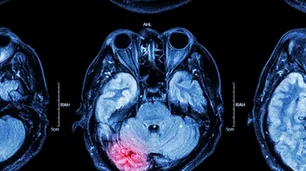

Traumatic Brain Injuries

Recovering Damages for Brain Injuries After a Chicago Car Accident: What You Need to Know